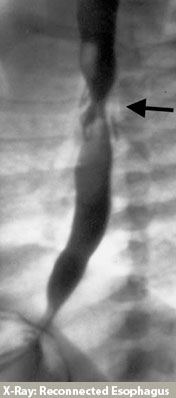

At the time of esophageal repair, a tube will be placed in your child's chest to drain any fluid that might accumulate near the surgical site. Several days after surgery a special x-ray, called a contrast esophagram, will be performed. This test is done to ensure there are no leaks along the esophageal repair. If the incision has healed, without a leak, the chest tube will be removed and feedings will be started by mouth. In some cases the esophageal repair may take longer to heal, and a leak will be visible on the x-ray study. If there is a leak, the chest tube will remain in place until the leaking stops. X-ray studies will be repeated every several days until the esophageal repair has completely healed.

If all is going well, a visit to our office at a specific time is not required. A visit to your child's Primary Provider, at one to two weeks after the discharge, is recommended. Children with esophageal atresia and tracheoesophageal fistula may develop esophageal narrowing (stricture) at the site of repair. If this occurs, your child will have trouble swallowing liquids or solids. If the problem is severe you may notice your child coughing or choking on food, vomiting, or refusing to take food or liquids. If you suspect there is a stricture call our office as soon as possible. We will arrange for a special x-ray called an esophagram, which will help identify any narrowing or stricture of the esophagus. Surgical dilation (stretching) of the esophageal stricture may be required and will be performed under anesthesia.